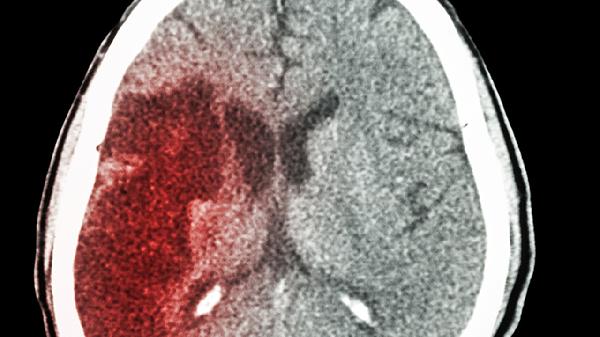

出血量是决定恢复速度的关键因素。少量出血小于10毫升对脑组织压迫较轻,通常1个月内可吸收;中等量出血10-30毫升需结合CT复查判断吸收情况,恢复期可能延长至2个月。出血后24小时内病情稳定者预后较好。

非功能区出血恢复较快。基底节区少量出血若未累及内囊,运动功能多在6-8周恢复;丘脑出血易影响感觉功能,需8-12周康复;小脑出血可能引起平衡障碍,需针对性前庭康复训练。